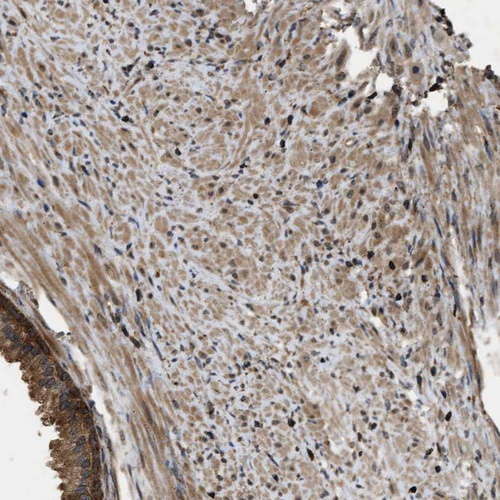

Immunohistochemical staining of human testis shows strong cytoplasmic positivity in cells in seminiferous ducts.